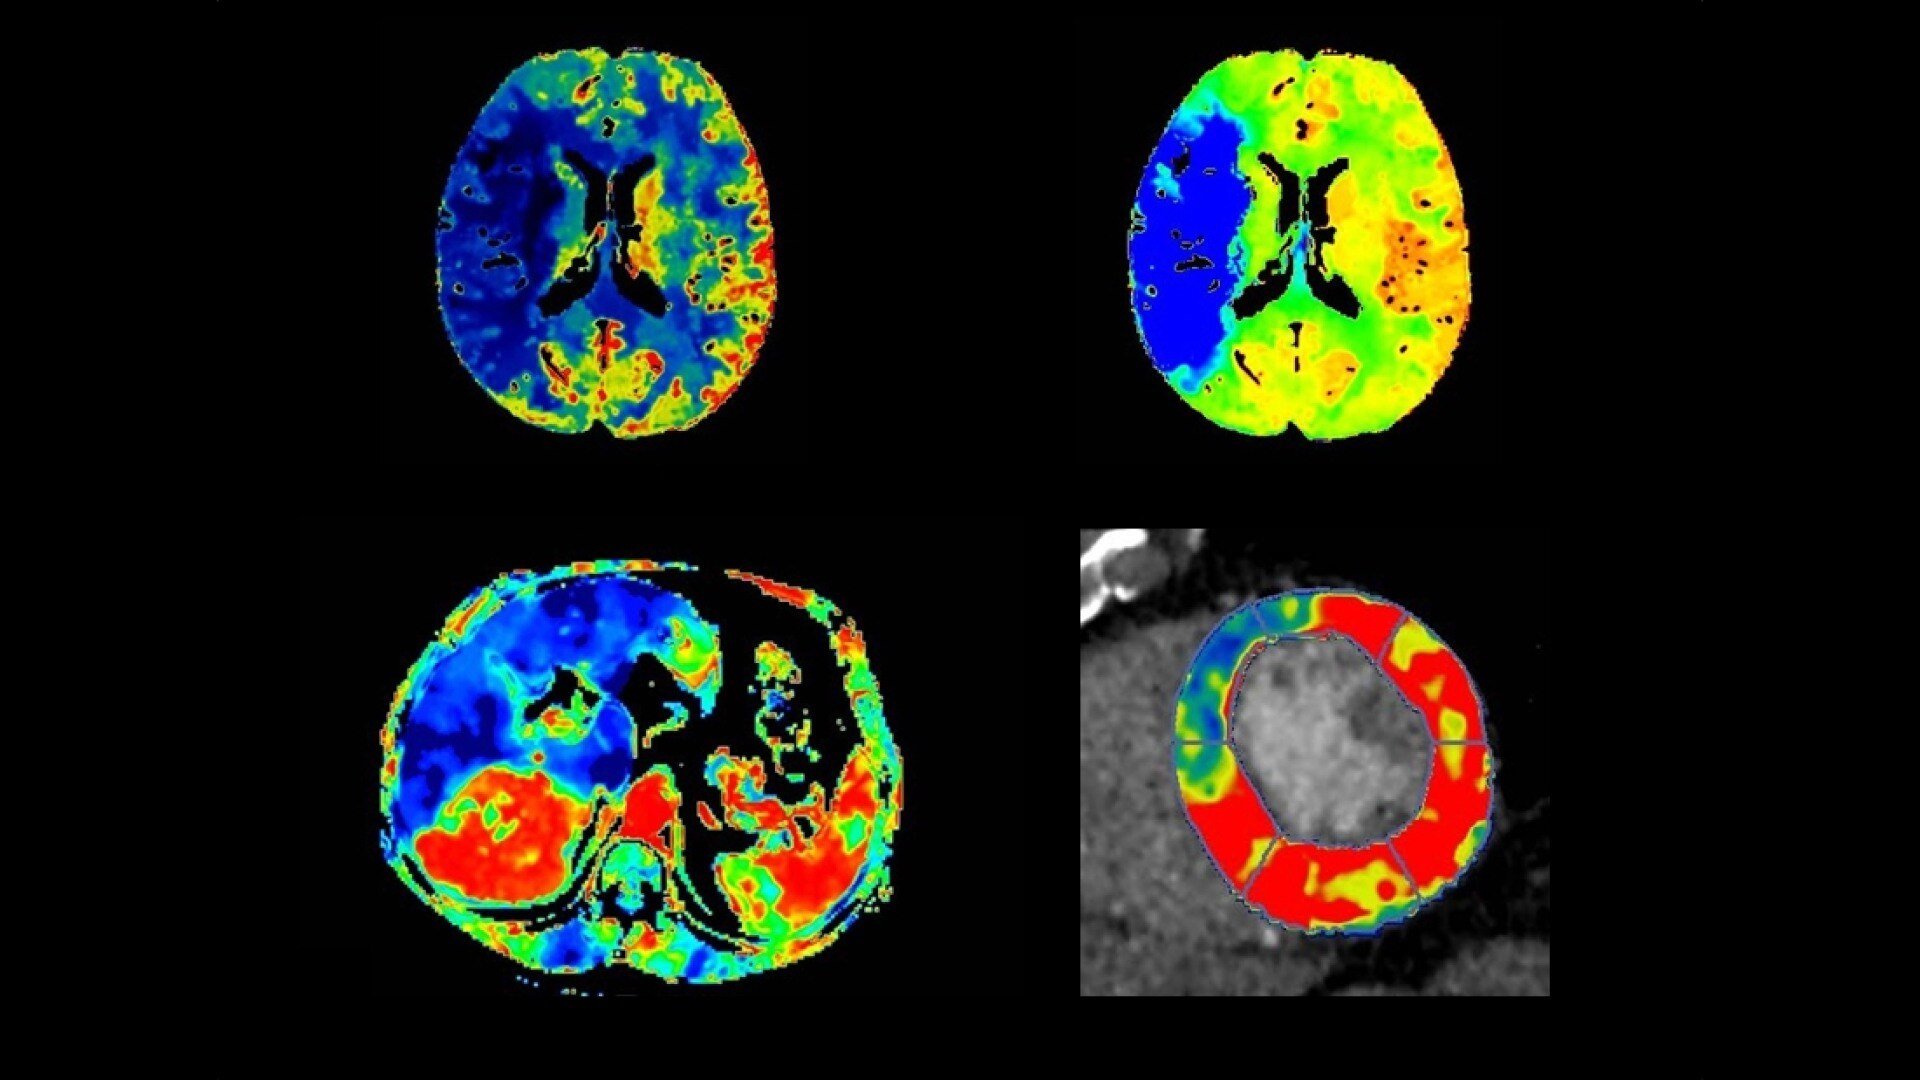

Brain perfusion

Easy-to-use automated workflow for CT stroke and tumor angiogenesis evaluation

Body perfusion

Optimized protocols for kidney, soft tissue, liver perfusion and other body tumors

CT Body Tumor Protocol

• Automatically produces functional maps once the user selects an artery using a simple and intuitive workflow

• Leverages most of the advanced algorithm settings that are part of the Brain Stroke protocol

• Optimized protocols for pancreas, prostate, kidney, soft tissue, spleen, bone and liver perfusion

Dynamic CT Myocardial Perfusion Protocol

The dynamic myocardial perfusion protocol is laid out in a series of three easy to follow steps. Start by selecting the series that has been generated from the non-rigid registration protocol and then follow the guided workflow:

• Cardiac Reformat– images are automatically orientated into short and long axis views

• Segmentation–define the valve plane and the apex of the heart. The software will then calculate the endocardial and epicardial borders and provide a 17 segmented map of the myocardium along with a graphed view for each segment.

• Functional Maps – the third and final step produces the quantitative data with the color overlay and bullseye maps for blood flow, blood volume, mean slope of increase and mean transit time.

03-dynamic-ct-myocardial-perfusion-protocol-featured-hero